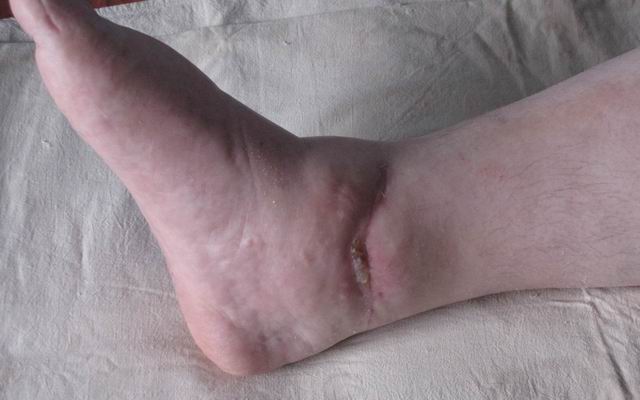

На прием обратилась женщина 50 лет с неправильно сросшимся переломом наружной лодыжки и наружным подвывихом стопы.

Травма в октябре 2009 года - подвернула стопу (на настоящий момент 6 месяцев): открытое повреждение правого голеностопного сустава: закрытый перелом наружной лодыжки с вывихом стопы кнаружи, разрыв дельтовидной связки (рана по внутренней поверхности около 8 см). При поступлении произведено вправление вывиха, трансартикулярная фиксация голеностопного сустава спицами и ПХО раны. Заживление раны осложнилось краевым некрозом, рана зажила вторичным натяжением. Около недели назад открылся свищ с серозно-гнойным скудным отделяемым. В настоящее время имеется отек, движения в голеностопном суставе резко ограничены, стопа в нейтральное положение не выводиться (угол около 5 градусов подошвенного сгибания), ходит (около 1 месяца) с частичной опорой, полная нагрузка болезненна.